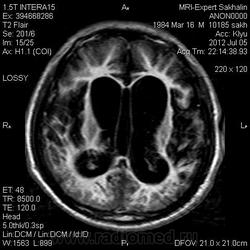

1 случай -локальная гемиатрофия.2 случай-диффузная.

Молодой человек после автомобильной аварии.3 года лежит.Двигаются только глаза.Зрелище душещипательное.

Евгений, конечно же, мои случаи не являются "чистой" атрофией-согласна.Мне пока не встречались случаи болезни Пика, Альцгеймера и другие "чистой воды" атрофии.Второй случай- состояние после длительной комы вследствие автодорожной травмы 3 года назад.Пациент проходил исследование в прошлом году , в этом родители привезли на динамику.